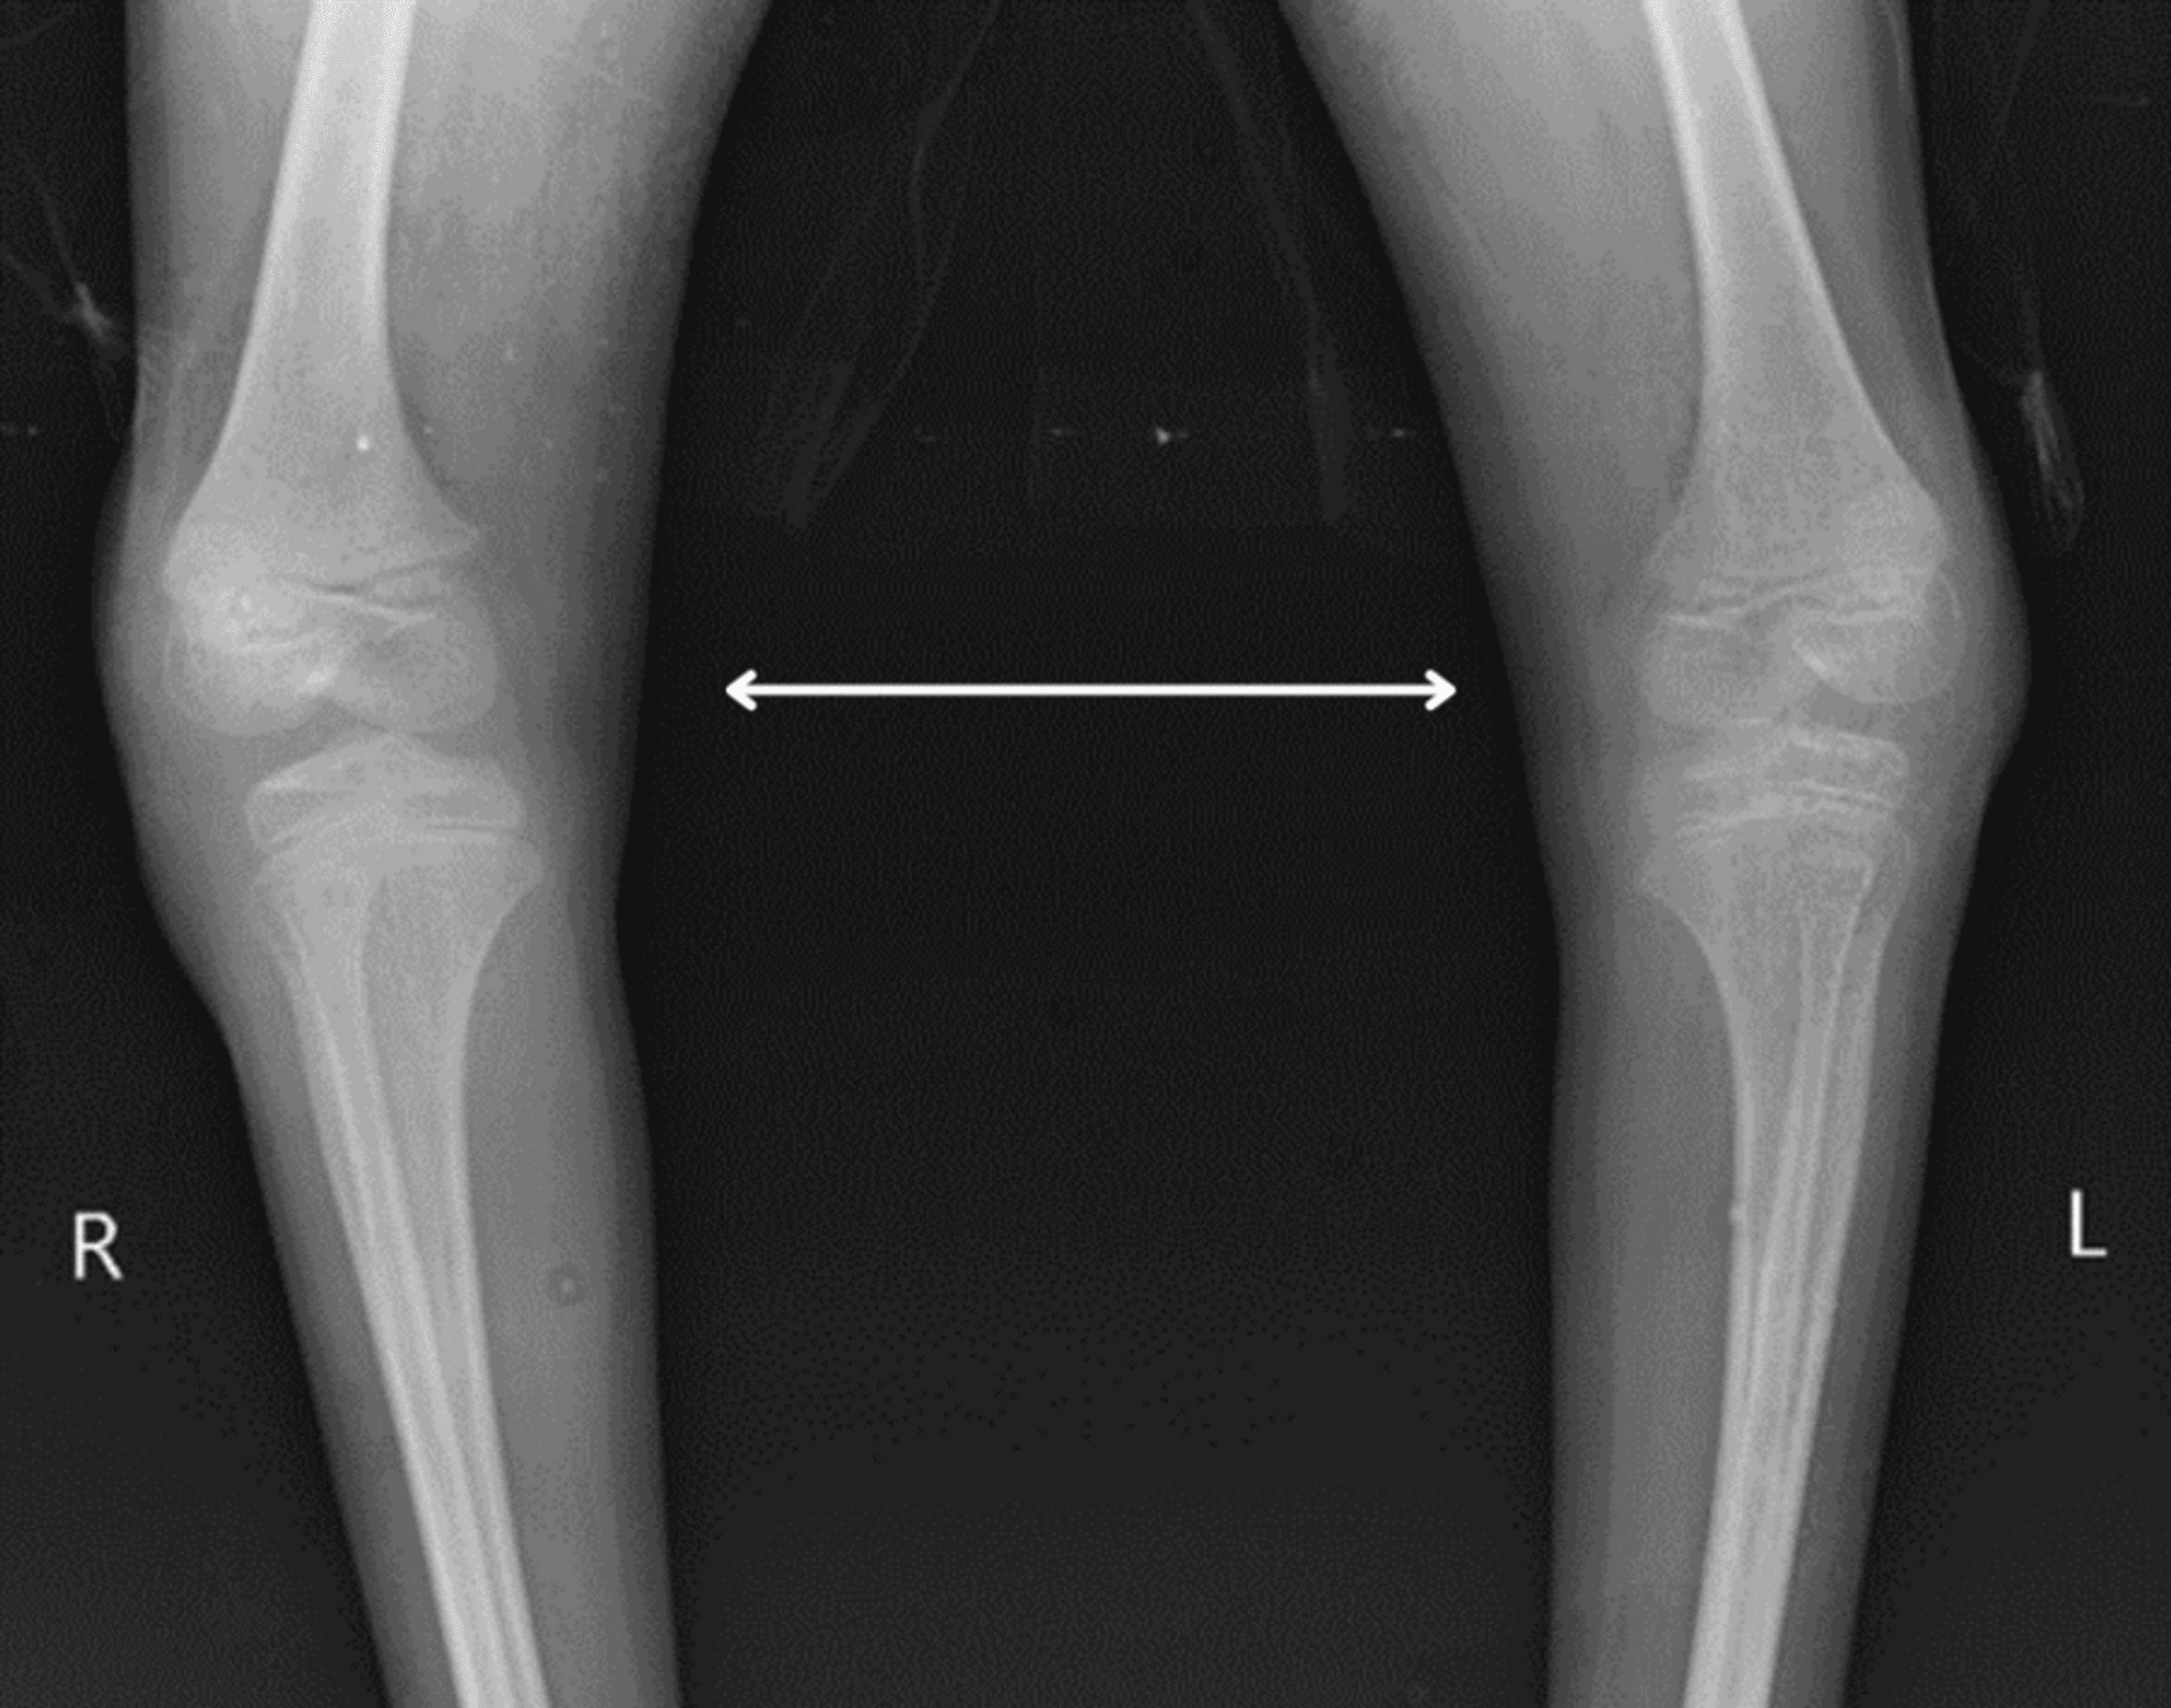

Treatment of talipes equinovarus after triceps surae intramuscular

From www.wjgnet.com

Treatment of talipes equinovarus after triceps surae intramuscular Talipes Equinovarus Physiotherapy Treatment this guideline covers the primary diagnosis and treatment of idiopathic clubfoot in children presenting with the deformity in the first 6. Identify interprofessional team strategies for improving. when you look at their foot, the bottom often faces sideways or even up. Another name for club foot is talipes equinovarus. Stretching and casting (ponseti method) surgery. treatment options. Talipes Equinovarus Physiotherapy Treatment.